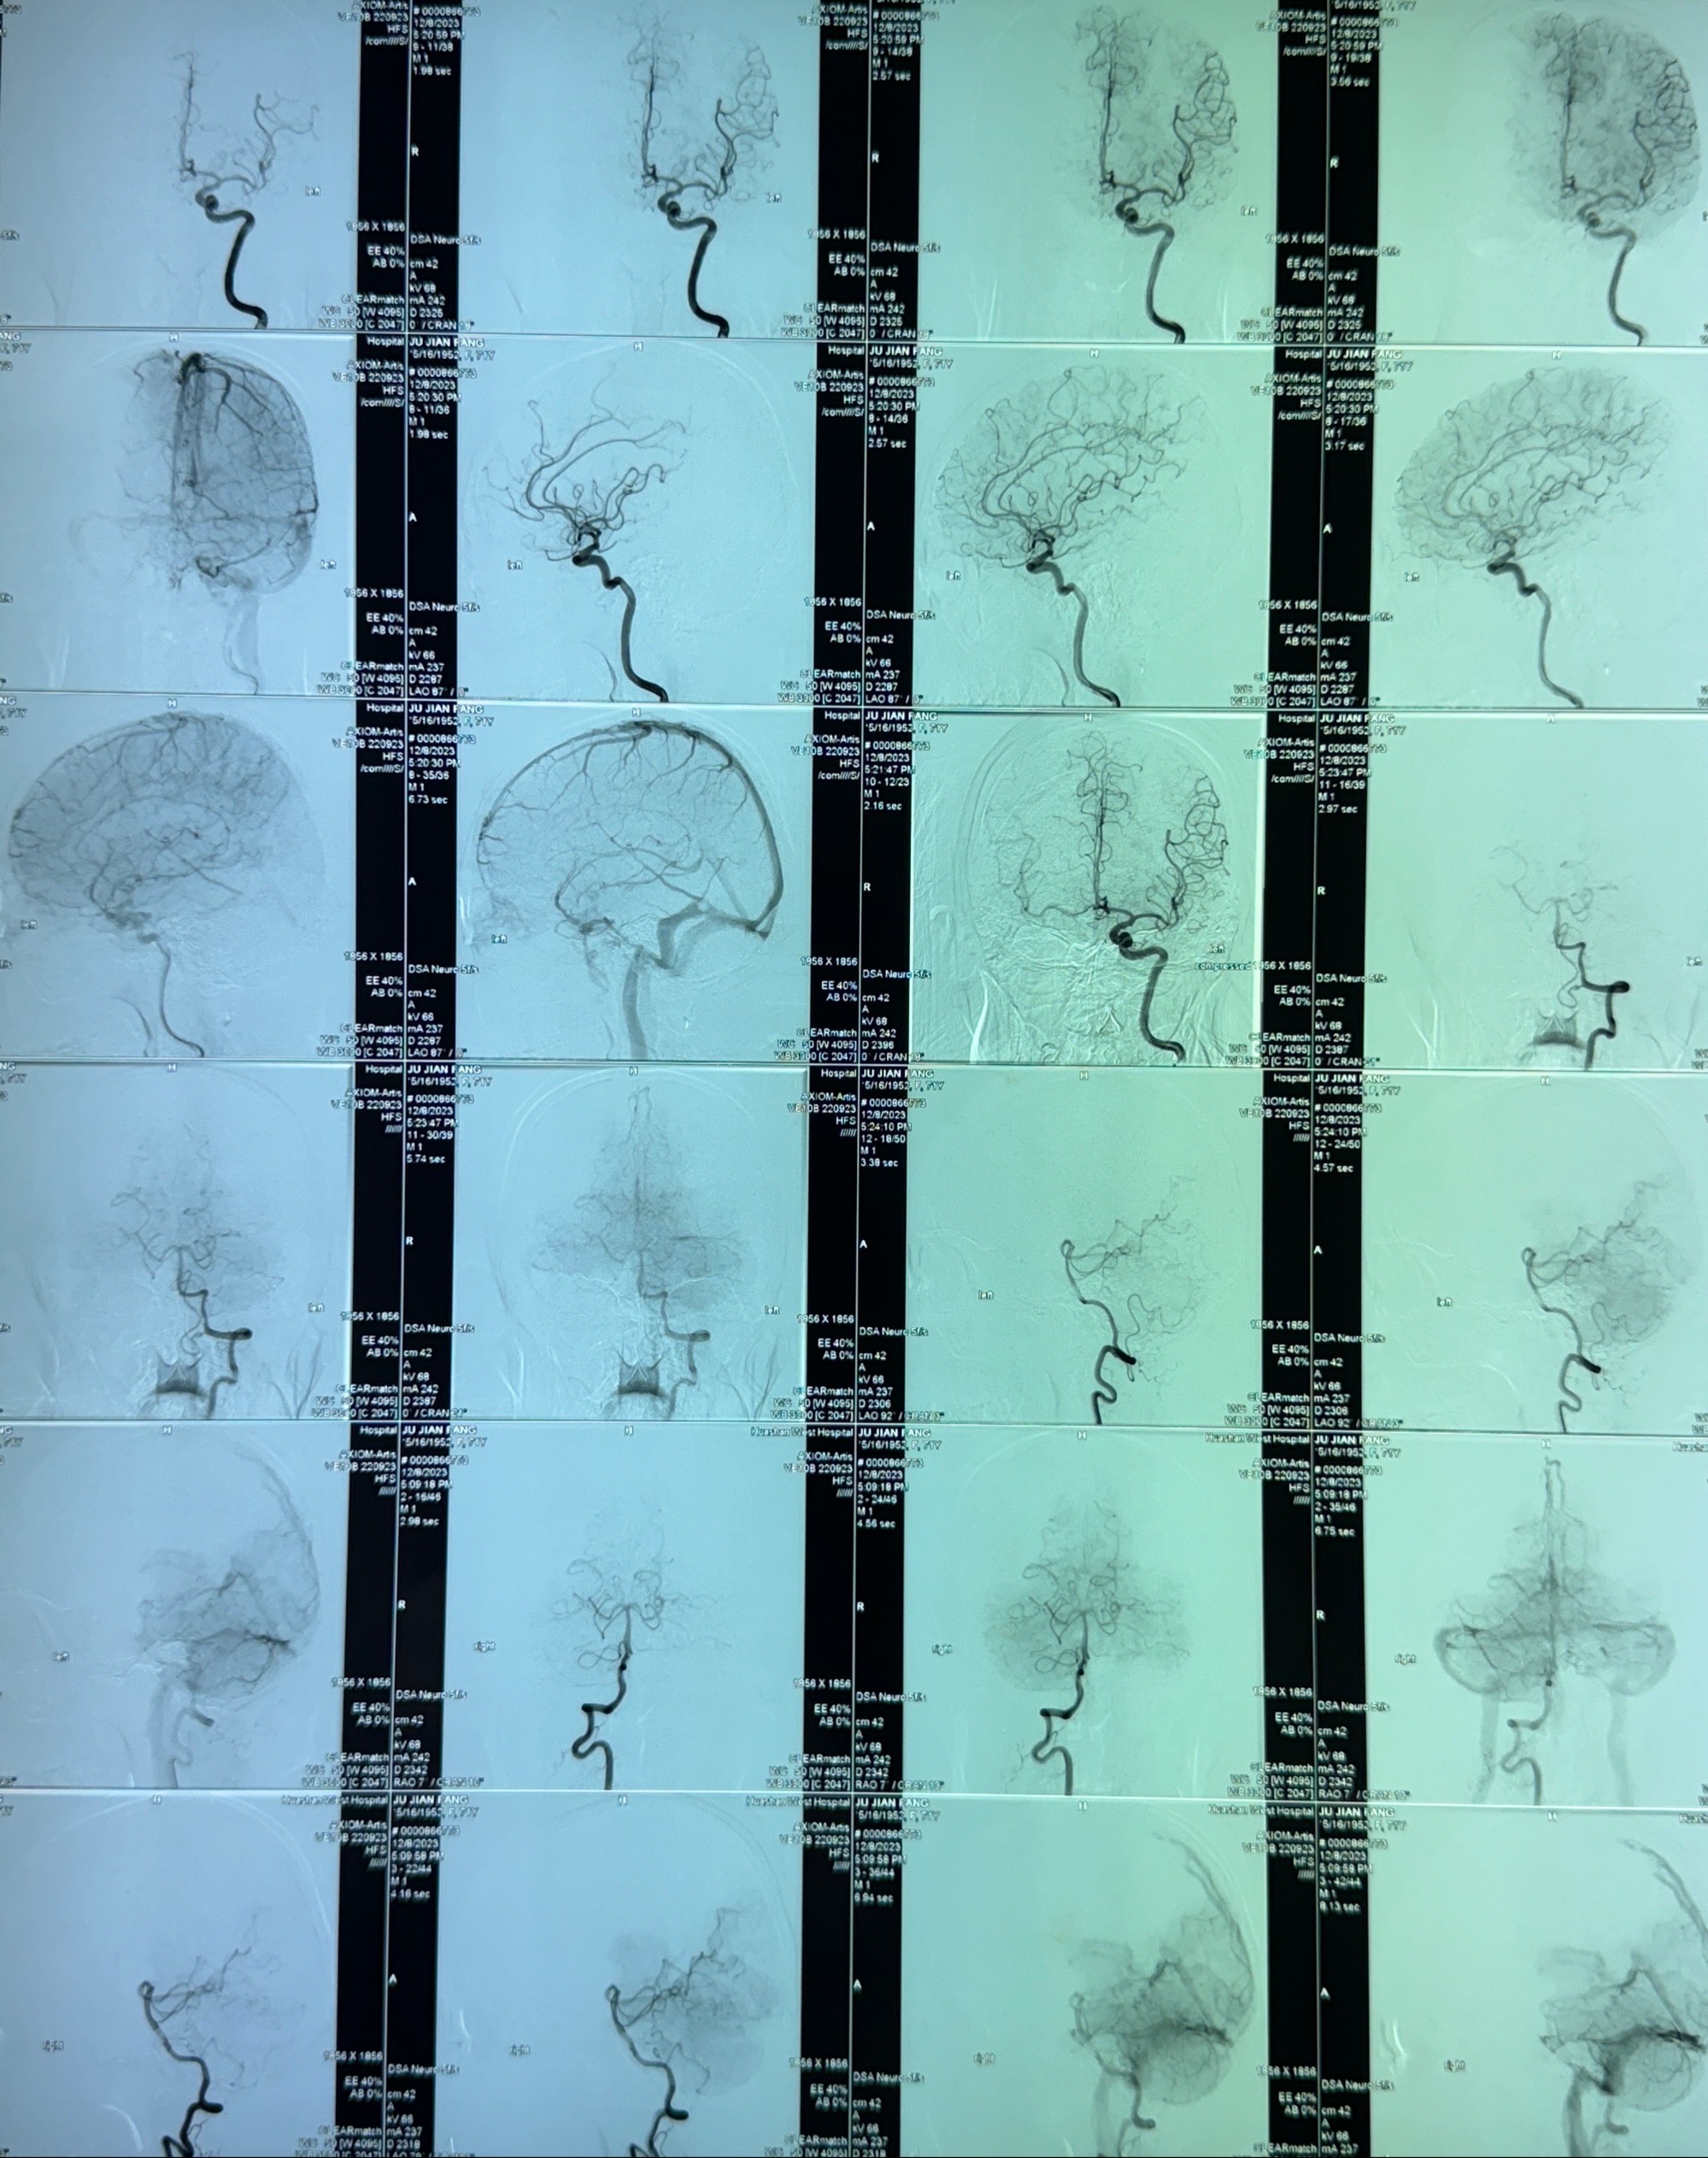

2023-12-08外院DSA:右侧颈眼动脉瘤,约13*12mm大小,压颈试验显示左右向及后向前代偿可

2023-12-18全麻下行DSA➕密网支架植入备弹簧圈辅助栓塞